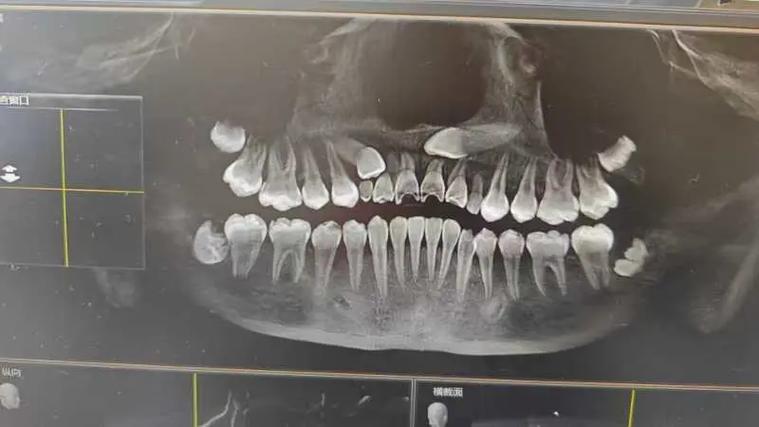

低位水平阻生齿的正畸治疗核心在于“解除阻生、引导萌出、保存功能”,通过科学设计牵引路径,将埋藏的牙齿移动至正常咬合位置,避免邻牙损害及颌骨破坏,治疗前需全面评估:临床检查需观察口腔黏膜状况、邻牙松动度及咬合关系;影像学检查是关键,通过CBCT可清晰显示阻生牙的萌出方向、牙根形态、与邻牙牙根及下颌神经管的距离,判断是否具备牵引条件;同时需研究模型分析咬合曲线,制定个性化方案。

此阶段需综合临床与影像学资料,明确阻生牙位置、萌出阻力来源(如骨阻力、邻牙阻力)及患者年龄(青少年颌骨生长潜力大,预后更佳),若邻牙已严重损坏或存在囊肿,可能需先拔除患牙,再对阻生齿进行牵引;若邻牙健康,则需设计支抗,为后续牵引提供稳定基础。

预后方面,多数低位水平阻生齿通过规范正畸牵引可成功萌出并行使功能,但若阻生牙位置过深、牙根弯曲或与神经管距离<1mm,可能需结合外科手术辅助,甚至无法保留而拔除,青少年患者因颌骨生长活跃,治疗周期更短,效果更佳;成年人则需更长时间保持,以防止复发。